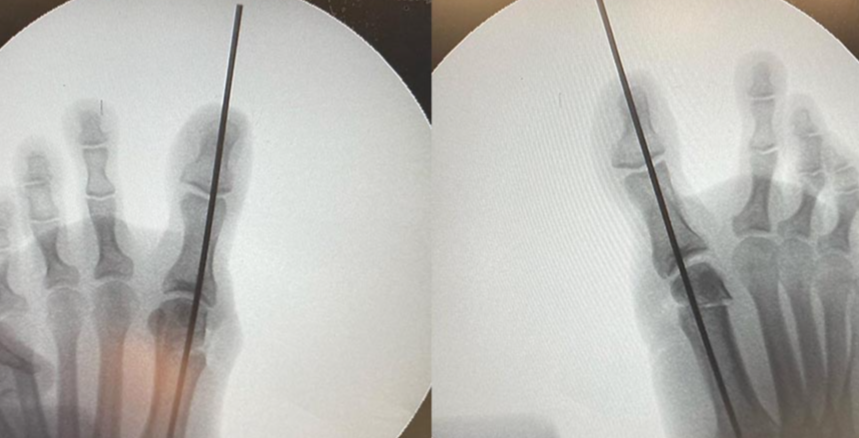

Операция Вальгусная Деформация Фото

Операция Вальгусная Деформация Фото 113 фотографий